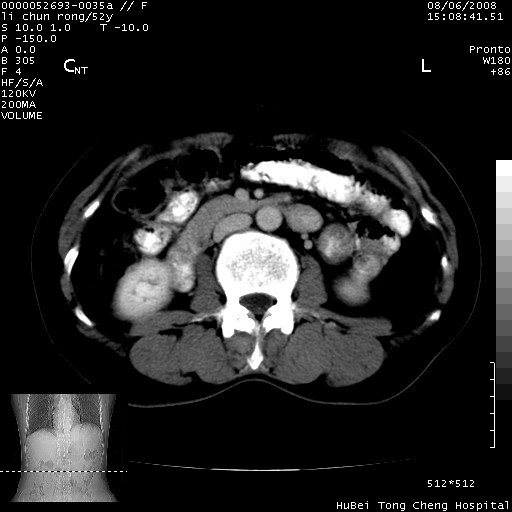

以下是引用云翔在2008-8-7 6:20:00的发言:[br]胰尾部囊性病变,考虑假囊肿,结合实验室检查疾病史

以下是引用zjzjr在2008-8-7 8:38:00的发言:[br]支持胰腺炎伴假囊肿形成,左肾小囊肿.少量腹水.

以下是引用随光逐影在2008-8-7 9:12:00的发言:[br]1)考虑胰腺炎伴假性囊肿形成可能性大;胰腺囊腺瘤待排。2)左肾小囊肿。3)少量腹水。